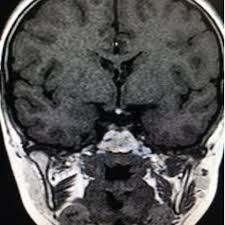

Pituitary and Neuroendocrinology. Pituitary stalk interruption syndrome PSIS is a rare congenital disorder characterized by a triad of a thin or interrupted pituitary stalk aplasia or hypoplasia of the anterior pituitary and absent or ectopic posterior pituitary EPP seen on magnetic resonance imaging MRI. Pituitary stalk interruption syndrome PSIS is a rare congenital disorder characterized by a triad of a thin or interrupted pituitary stalk aplasia or hypoplasia of the anterior pituitary and absent or ectopic posterior pituitary EPP seen on magnetic resonance imaging MRI.